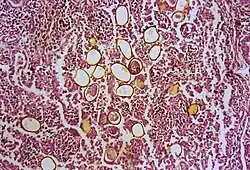

Photomicrograph showing ova within lung parenchyma